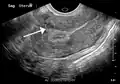

Physical examination and ultrasound are sufficient for diagnosing uterine fibroids in the majority of people. When ultrasound findings are inconclusive, magnetic resonance imaging (MRI) may be able to confirm the diagnosis of uterine fibroids in most cases. In addition, MRI can identify benign uterine fibroids with atypical imaging features and fibroids with variant growth patterns. MRI can also identify other uterine (e.g. adenomyosis, endometrial polyps, endometrial cancer) and extrauterine (e.g. benign and malignant ovarian tumors, endometriosis) disorders that may mimic the appearance of uterine fibroids and/or contribute to the patient's symptoms.[38] However, a small proportion of uterine fibroids can mimic other malignant uterine tumors (e.g. leiomyosarcoma) on all available imaging modalities (e.g. ultrasound, CT, MRI and PET-CT).[38]

Malignant tumors of the uterine wall (e.g. leiomyosarcoma) are very rare. Findings suggestive of a malignant uterine tumor rather than a benign fibroid include, fast or unexpected growth (particularly after menopause), interruption/effacement of the endometrial stripe, lymph node enlargement, invasion of adjacent organs and metastases to distant organs (e.g. lung). MRI findings suggestive of a malignancy include nodular/ill-circumscribed tumor margins, intermediate/high T2-weighted signal intensity of the solid tumor components, regions with high signal T1-weighted sequences in keeping with subacute hemorrhage, fine/wispy enhancement of the solid parts of the tumor, and restricted diffusion on diffusion-weighted imaging (DWI).[38] A biopsy is rarely performed and if performed, is rarely diagnostic. Should there be an uncertain diagnosis after ultrasounds and MRI imaging, surgery is generally indicated.[39]